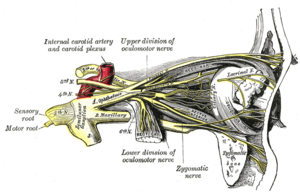

التعصيب

- الحس العام: عن طريق فروع من أول فرعين للعصب مثلث التوائم (العيني والفكي العلوي). فالأجزاء الأمامية لجوف الأنف يتم تعصيبها بواسطة العصب الغربالي الأمامي فرع العصب الأنفي الهدبي (الذي بدوره يتفرع من العصب العيني)، أما الأجزاء الخلفية من جوف الأنف يتم تعصيبها عبر فروع للعقدة الجناحية الحنكية والتي تصلها ألياف من العصب الفكي العلوي.

- حس الشم: عن طريق ألياف العصب الشمي التي تعبر الصفيحة المصفوية.[1]